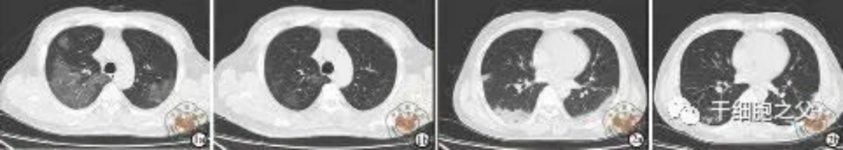

與安慰劑組相比,人臍帶間充質(zhì)干細(xì)胞修復(fù)組全肺病變體積改善了10.8%,并且人臍帶間充質(zhì)干細(xì)胞修復(fù)組在每一個(gè)隨訪節(jié)點(diǎn)都顯示出固體組分病變體積比例減少。此外,人臍帶間充質(zhì)干細(xì)胞組有17.9%的患者在12個(gè)月時(shí)CT圖像變?yōu)檎#参縿┙M沒有。

細(xì)胞輸注后,炎癥指標(biāo)改善,復(fù)查胸部CT提示雙肺病灶較前吸收,呼吸道癥狀改善,新型冠狀病毒核酸檢測連續(xù)2次陰性,治愈出院。

研究結(jié)果:細(xì)胞輸注后,炎癥指標(biāo)改善,復(fù)查胸部CT提示雙肺病灶較前吸收,呼吸道癥狀改善,新型冠狀病毒核酸檢測連續(xù)2次陰性,治愈出院。